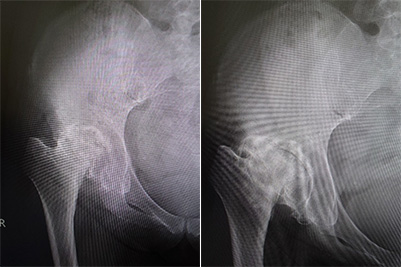

末期の変形性股関節症であっても幹細胞注入とPRPにより関節軟骨の層ができて歩行可能となった例。

60台女性で強い股関節痛にずっと悩まされてきた方です。近医では人工関節手術を勧められていましたが自分の骨で歩きたいとの希望が強く再生治療を行うこととしました。

一回の幹細胞注入と3回のPRP注入により日常生活では困らないレベルまで痛みが改善できいい状態が維持できています。

投与前(写真左):関節軟骨の消失と関節の破壊

投与後(写真右):関節裂隙の軟骨像層が出現と骨頭の回復もある